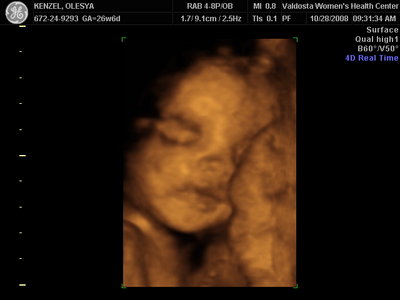

Ксюнь, а мы вообще не поняли. Она на всех фотках разная, да еще размытость такая. Пуповина то на носу болталась, то руками-ногами закрывалась. Главное что четкости нет совсем. Лоб у мужа тоже большой, а носы и губы зачастую на 3Д-4Д выходят разамазанно-пухло-приплюснутыми Поставлю для наглядности фотку моей средней-Джианки с 3Д УЗИ, там видно черты намного лучше и она на себя ту похожа сейчас, хотя родилась мне совсем на фото УЗИ не казалась похожей.

KENZEL,OLESYA_3.JPG [ 56.84 КБ | Просмотров: 1210 ]

Еще одна Джианнка:

KENZEL,OLESYA_5.JPG [ 60.02 КБ | Просмотров: 1293 ]